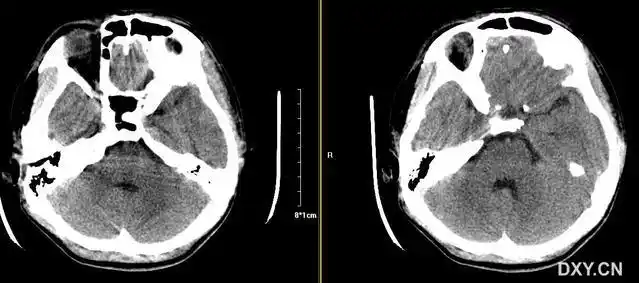

头颅 ct 示双侧额叶,顶叶及枕叶低密度灶,内有少许高密度灶,脑组织

颅脑创伤-神经重症病例周刊(第22期)丨双侧额叶脑侧裂伤一例